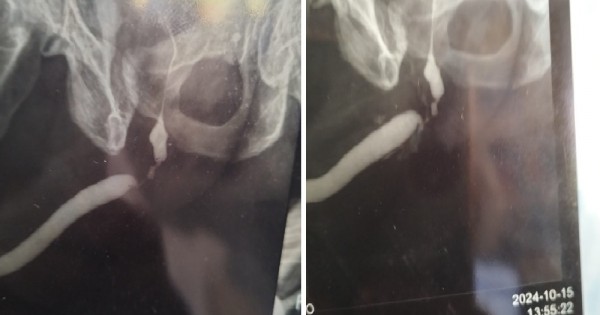

URETHRAL STRICTURE is a narrowing of the urethra—the tube that carries urine out of the body—caused by scar tissue from injury, infections, or medical procedures. This narrowing can lead to a weak or interrupted urine stream, difficulty starting urination, frequent infections, and discomfort.

• Diagnosis: Through a physical exam, imaging tests, or endoscopy.

• Treatment: May include dilation (widening the urethra) or surgical repair (urethroplasty) in severe cases.